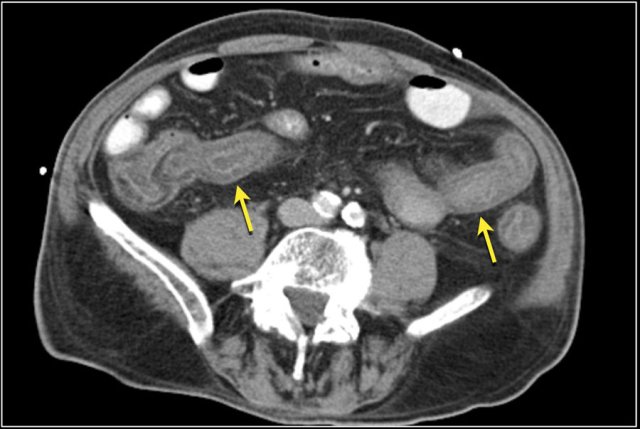

The images show a short obstructing circular mass in the jejunum (yellow arrow) with enlarged lymph node (red arrow).

This proved to be an adenocarcinoma.